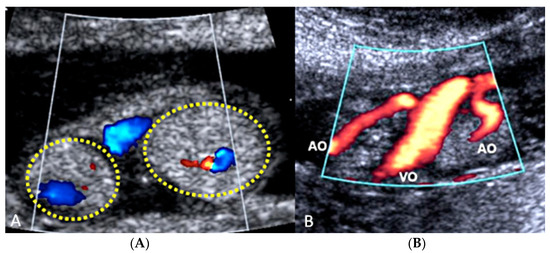

3.2.10. Single Umbilical Artery

3.2.11. Umbilical Cord Varix